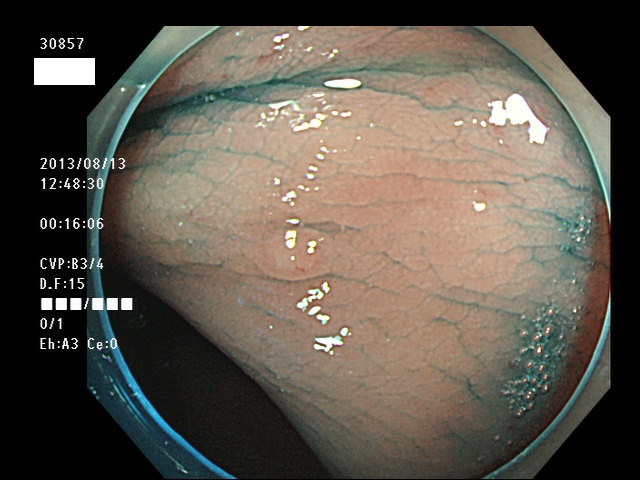

微小カルチノイドの診断

直腸の微小カルチノイドの診断は最も難しい問題です

微小とはいえ、カルチノイドは悪性であり、肛門に近い場所に好発するために、見落とすと数年後には「人工肛門」になる危険があります

進行したカルチノイドの診断は容易なのですが、カルチノイドは「粘膜下腫瘍」と言いまして、は表面が正常粘膜で被われているために微小ですと「単なる過形成結節」「単なる炎症性の隆起」と区別がつかないのです

下記の写真は全て、当院で診断された微小カルチノイド(悪性)ですが、いかに診断が困難かお分かりいただけるでしょう。このような微小病変でさえも見落とせば人工肛門の危険が潜んでいる訳です。